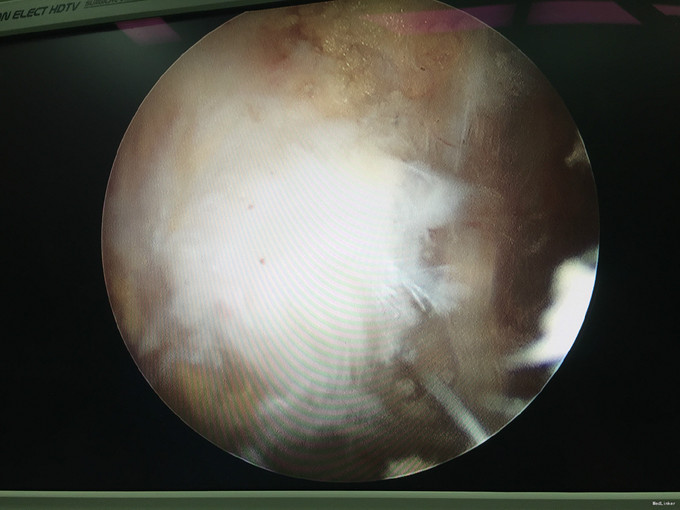

入院诊断:右肩峰下撞击综合症、右肩峰占位 治疗:右肩关节镜下肩峰成形,占位切除术

随访:患者术后感觉症状明显好转,肩关节活动度也较前改善。 讨论:该肿块性质尚无定论,仍需较长期的随访观察。请问各位专家,就目前的病史资料如何考虑该占位性质?